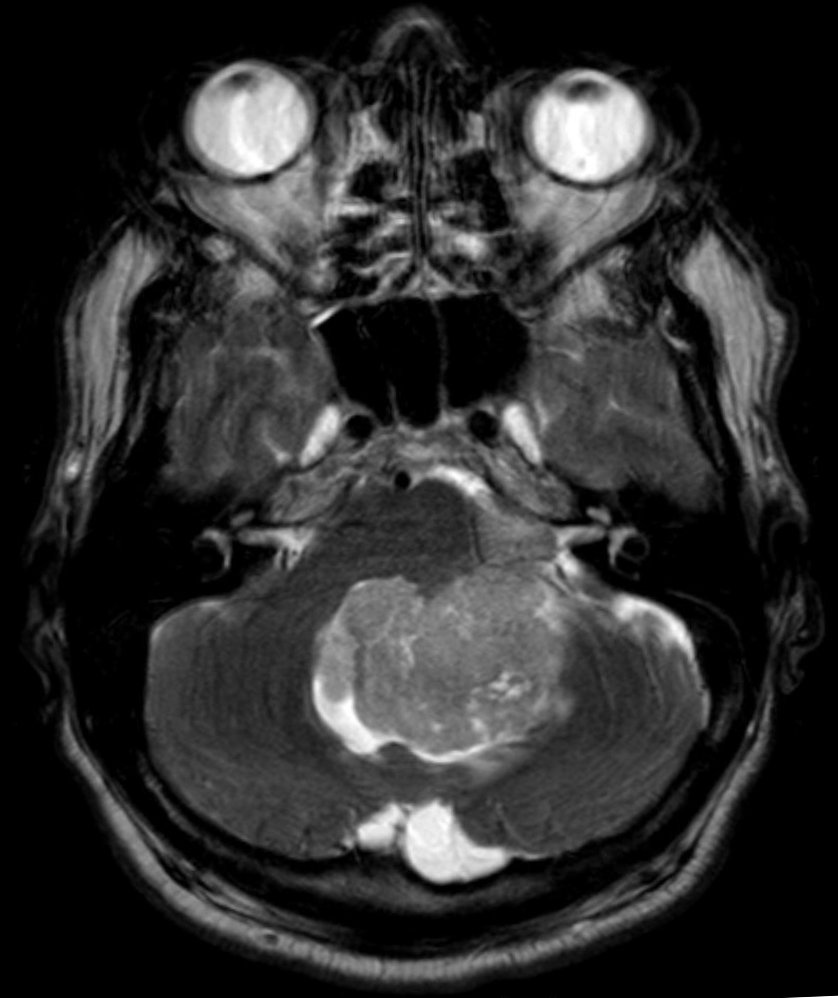

Axial T2Sagital FLAIR

Axial T1Axial T1 GadAxial T1 Gad/fat sat

For a detailed discussion of ependymoma imaging see Radiopedia for an excellent discussion on ependymoma imaging by Weerikoddy and Galliard.

MRI Brain

Careful examination of the entire neuraxis is required to assess for the presence of CSF seeding.